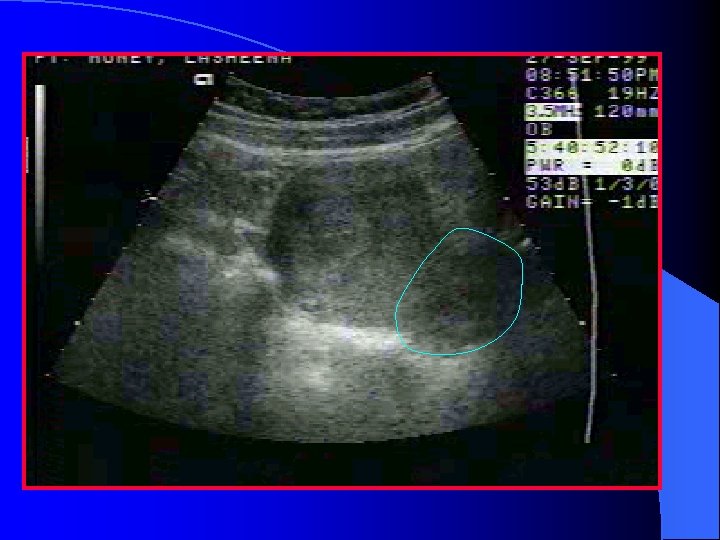

Ruptured Ectopic Pregnancy Free fluid or blood in the cul-de-sac or the intra-peritoneal gutters (hemoperitoneum) This finding and a positive pregnancy test essentially makes the diagnosis!

clot Clot/fluid